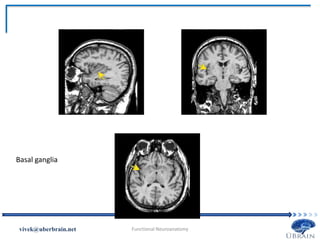

• Basal ganglia: A collection of subcortical nuclei in the

forebrain.

 Lie beneath the anterior portion of the lateral ventricles.

 The major parts: caudate nucleus, putamen, and the globus

pallidus.

 These structures are involved in the control of movement

(frontal lobe).

 Parkinson’s disease results from degeneration of the

connections between the midbrain and the caudate nucleus

and putamen.